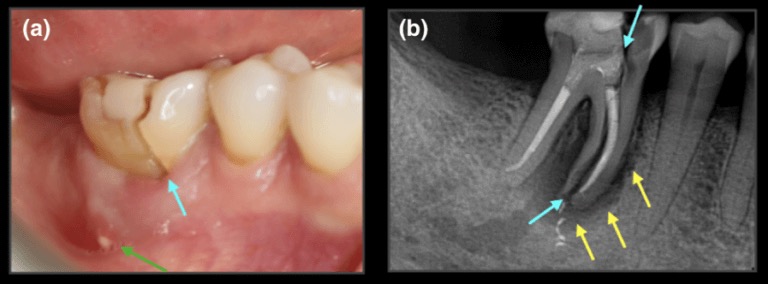

2️⃣ 牙齒可能裂掉(最常見的急診原因之一)

包括:

• 裂痕延伸

• 裂到牙髓

• 裂到牙根

嚴重時可能只能拔除。